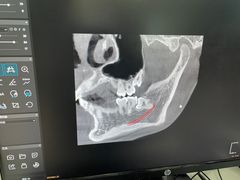

• 牙博士口腔品牌连锁(杨浦店)

• -牙博士口腔品牌连锁(杨浦店)

你的EVO | 23-04-26